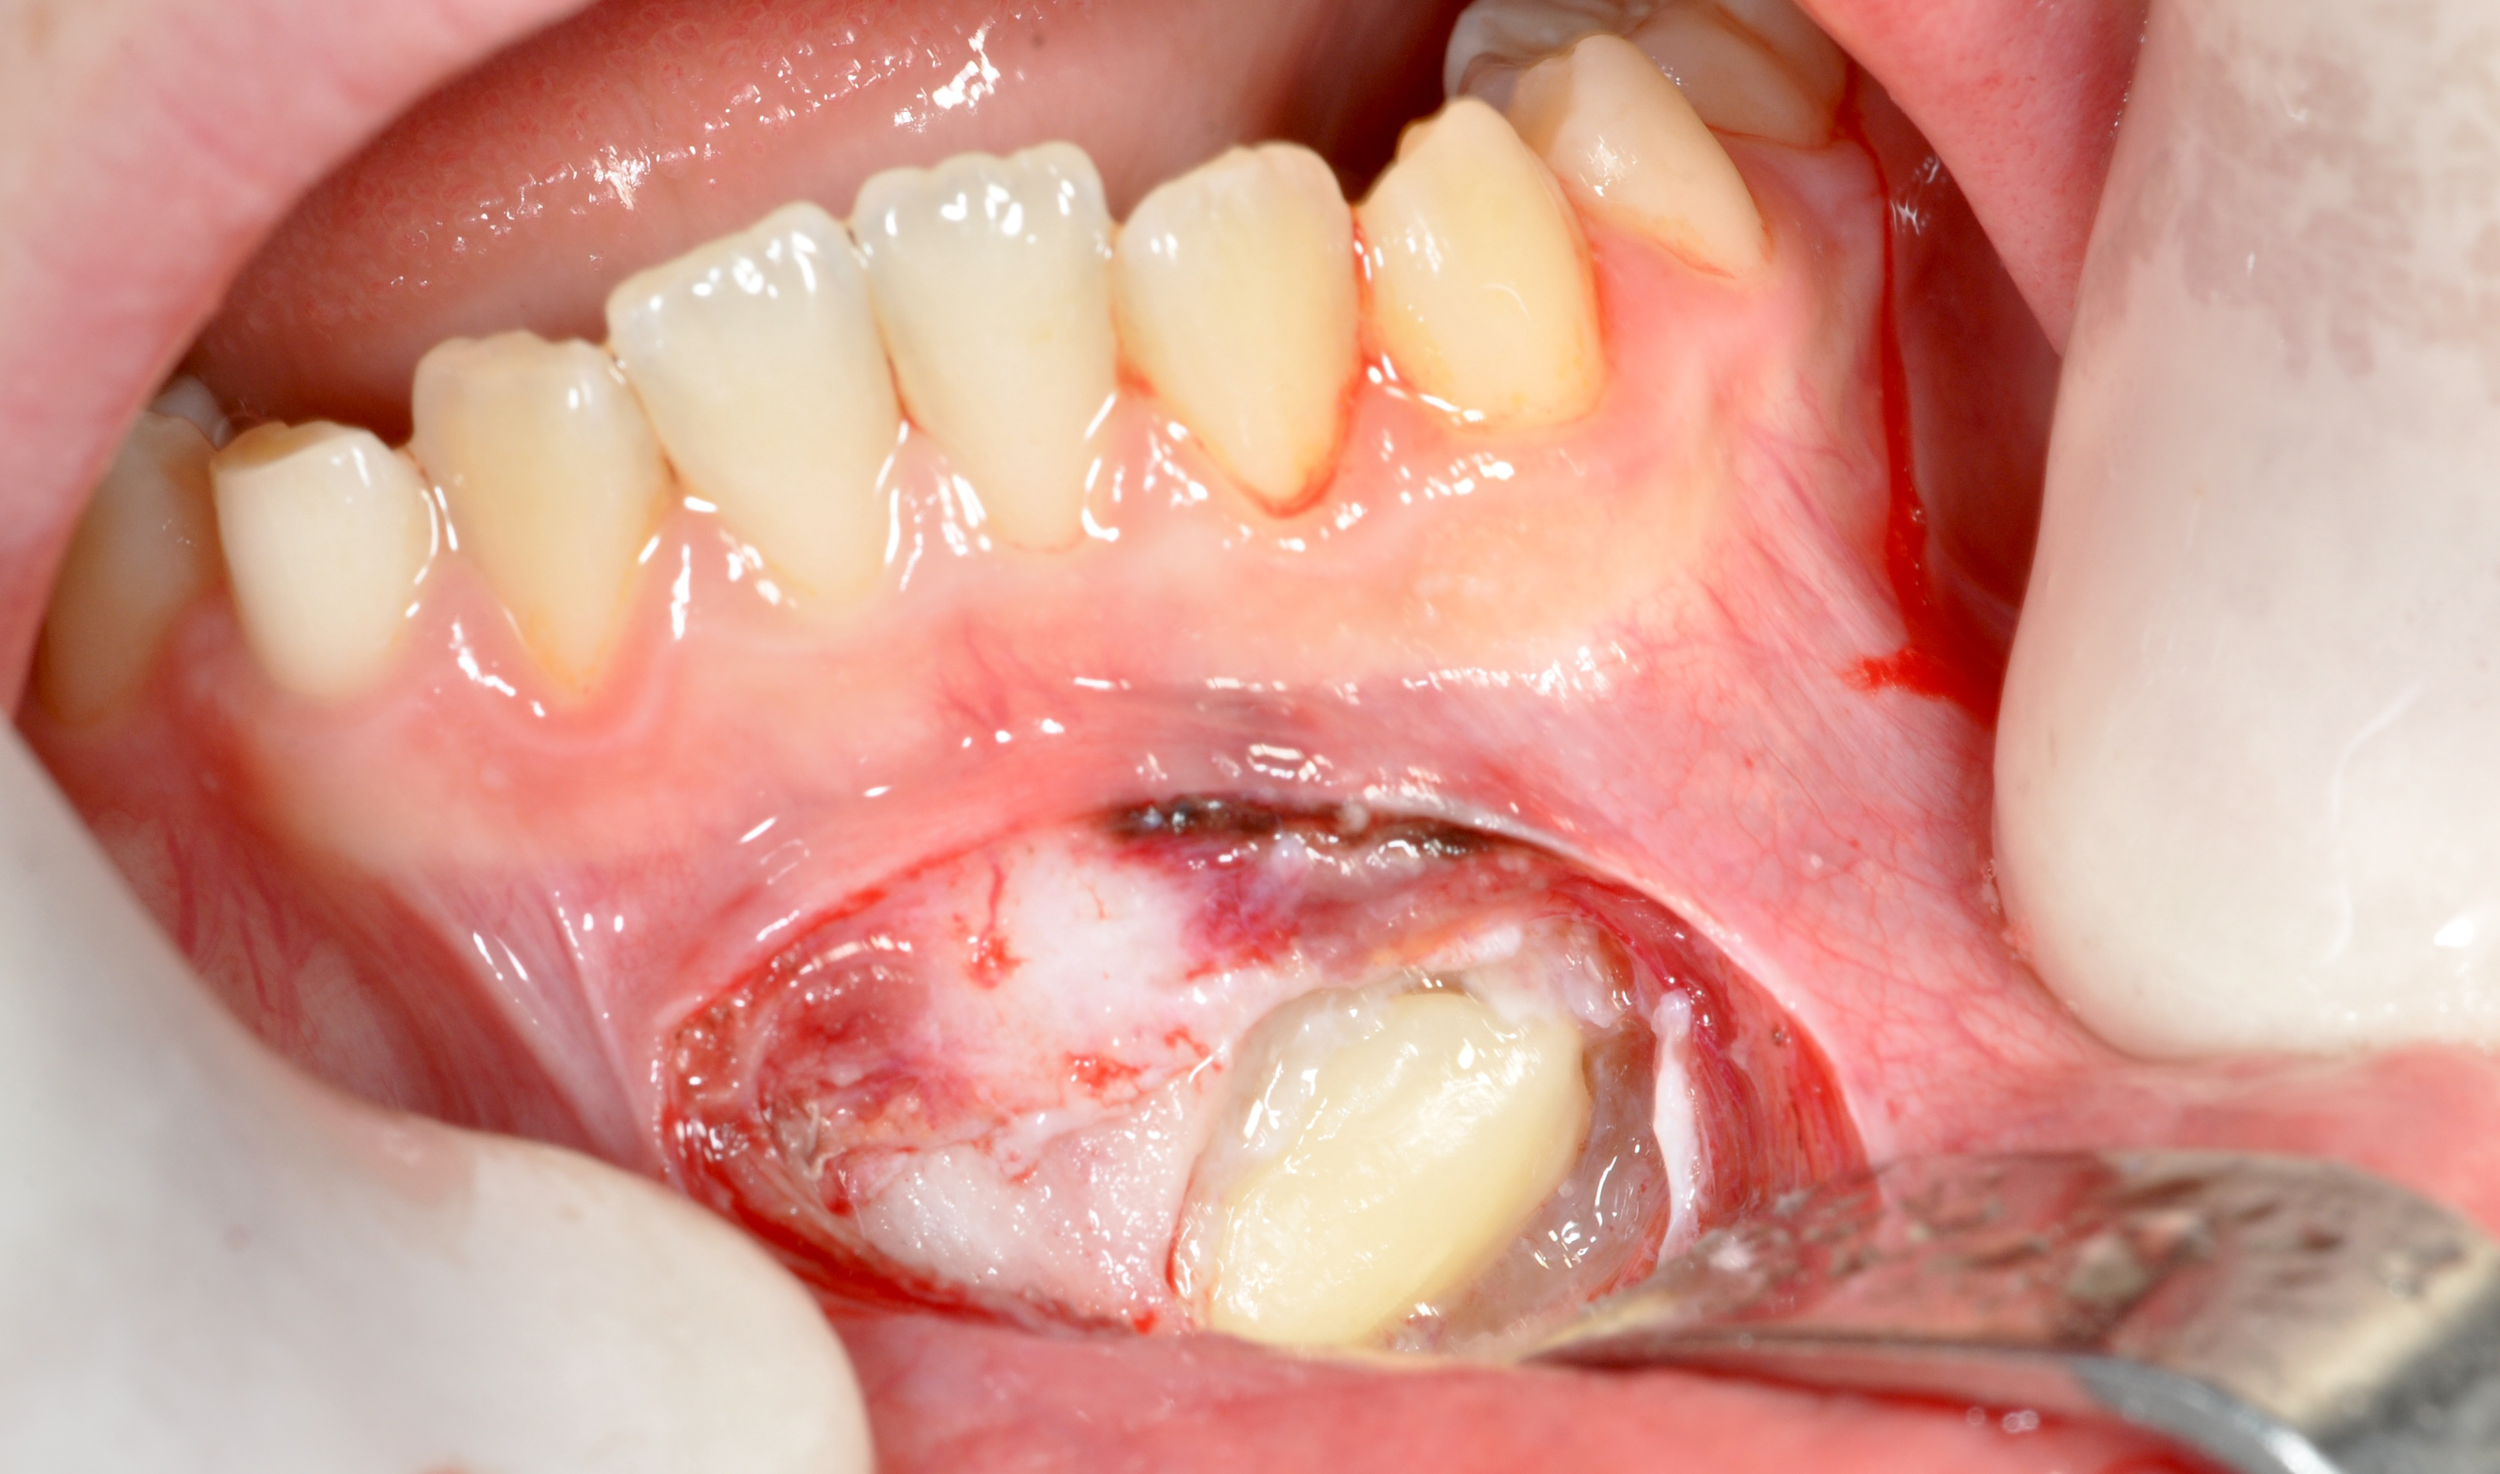

CASO 2

Estrazione di canino incluso in paziente pediatrico